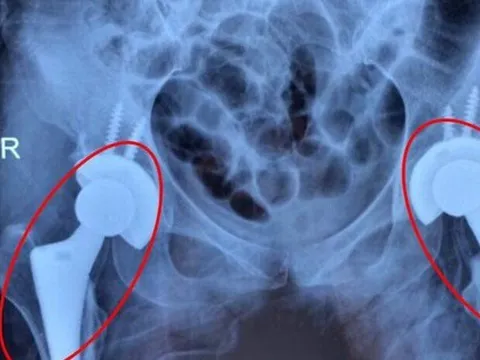

Nhiều người trẻ bị mục xương vì chất kích thích ai cũng dùng

Tắc mạch máu diễn tiến âm thầm khiến nhiều bệnh nhân bị mục cả 2 khớp háng, đối mặt nguy cơ tàn phế. Bác sĩ cảnh báo, nguyên nhân dẫn tới tình trạng trên là do người bệnh lạm dụng rượu bia. Giải pháp để cứu bệnh nhân là thay cả 2 khớp háng.